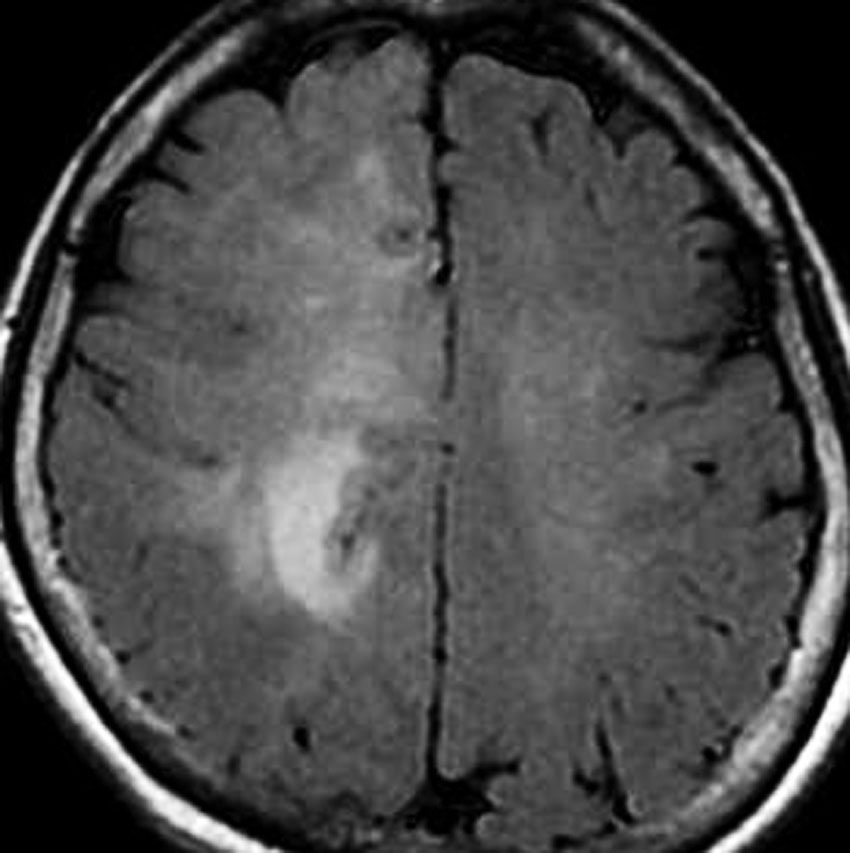

フレア画像です。左上前頭回の星細胞腫ですが,境界がとてもはっきりしていて限局性 localized single gyrus glioma です。びまん性 diffuseには見えません。IDH1の変異があり,1p/19qの欠失はないので星細胞腫グレード2です。上の例とは全く違う臨床像を示しますが,分子病理でも区別はつきません。頑張って早めに全摘出して治してしまった方がいいタイプです。再発を避けるために,supratotal resectionと言って,周囲の正常脳組織も10mmくらい余分に摘出します。